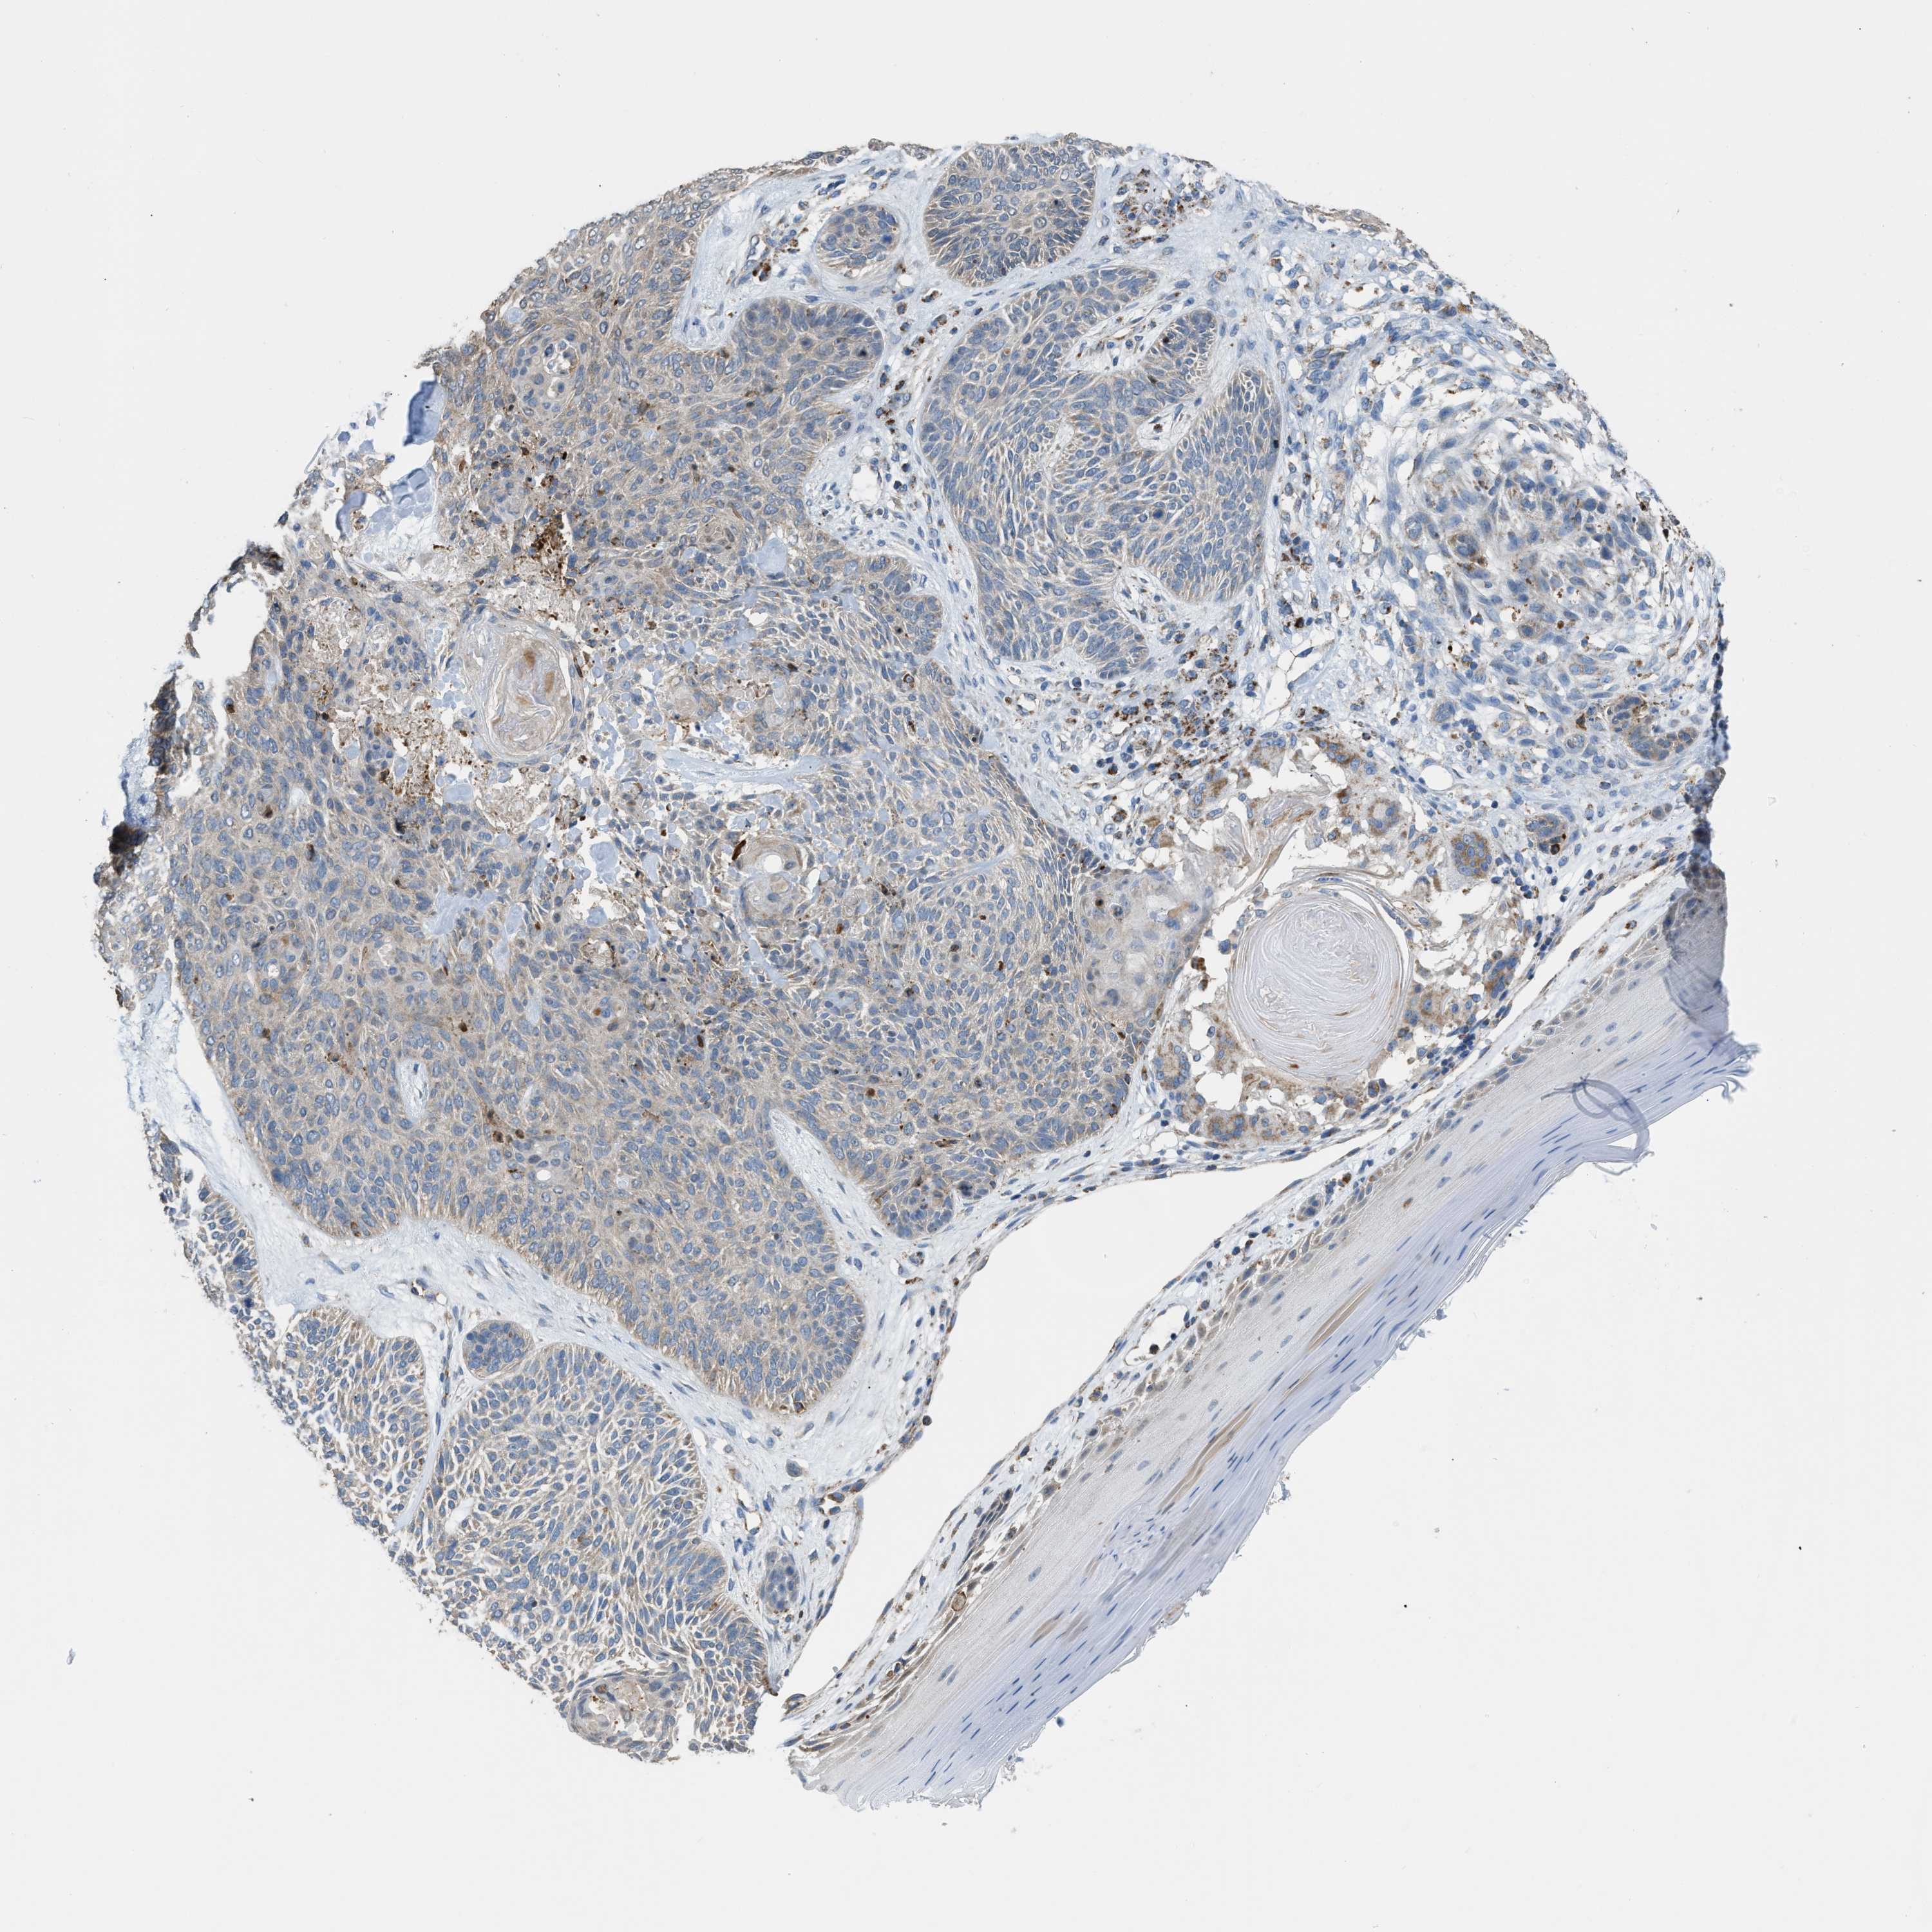

CANCER SKIN CANCER Show tissue menu

Basal cell and squamous cell cancer

SKIN CANCER - Protein expressioni

A mouse-over function shows sample information and annotation data. Click on an image to view it in a full screen mode. Samples can be filtered based on level of antibody staining by selecting one or several of the following categories: high, medium, low and not detected. The assay and annotation is described here.

Each image is clickable and will lead to virtual microscopy that enables deeper exploration of all samples and also displays staining intensity scores, fraction scores and subcellular localization as well as patient and tissue information for each sample.

Antibody HPA018910

Basal cell carcinoma

Squamous cell carcinoma, NOS

Squamous cell carcinoma, metastatic, NOS